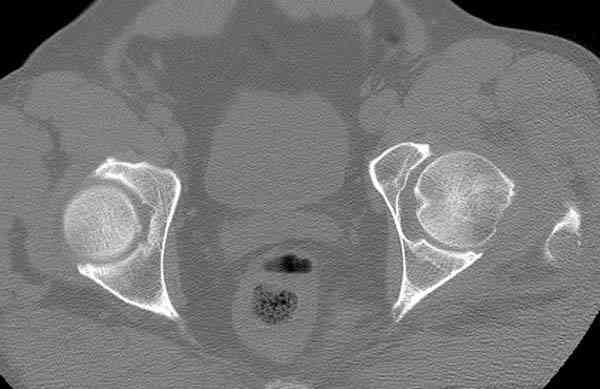

На второй день (7) обнаружен пропущенный перелом,

сделаны Компьютерная Томограмма

и проведены шурурпы через и спереди штифта без удаления.